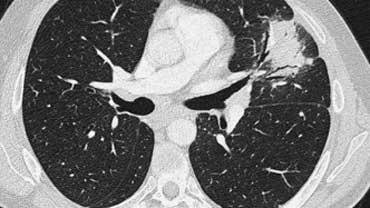

Đây là một trường hợp sarcoidosis phế nang.

Hãy cuộn qua các hình ảnh.

Hình ảnh trông giống như tăng tỷ trọng dạng kính mờ, nhưng khi quan sát kỹ hơn có thể nhận thấy rằng sự tăng tỷ trọng này là kết quả của nhiều nốt nhỏ tập hợp lại.

Cũng lưu ý hạch to rốn phổi.